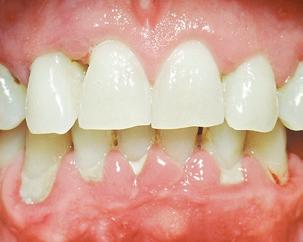

How healthy is your smile?

Stage IV –Severe Periodontitis

The American Academy of Periodontology (AAP) released a comprehensive update for the classification and documentation of periodontal and peri-implant diseases and conditions. This comprehensive update was developed and implemented because of the overwhelming information confirming the link between oral health and whole-body health. The first update the dental profession has seen since 1999, the updated classifications include a framework for staging and grading as well as defining the distribution of disease.

The staging consists of the severity of the disease and the complexity for disease management, while the grading defines the rate of progression, a patient’s overall health, social habits, and the expectation of how well the disease will respond to treatment. Distribution expresses if the disease is localized or generalized.

This new classification and documentation of periodontal disease takes into consideration a patient’s current oral condition, health history, and risk factors. This information helps assess how serious an infection in the gingival tissue and underlying bone can be for a patient’s oral health and whole-body health.